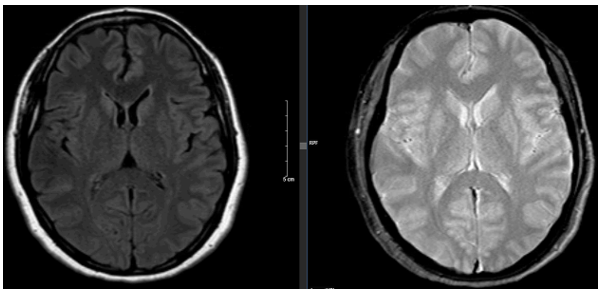

-     Cộng hưởng từ sọ não (trước mổ): Hiện không phát hiện tổn thương nghi ngờ thứ phát.

Hình 3: Hình ảnh chụp cộng hưởng từ sọ não không phát hiện di căn